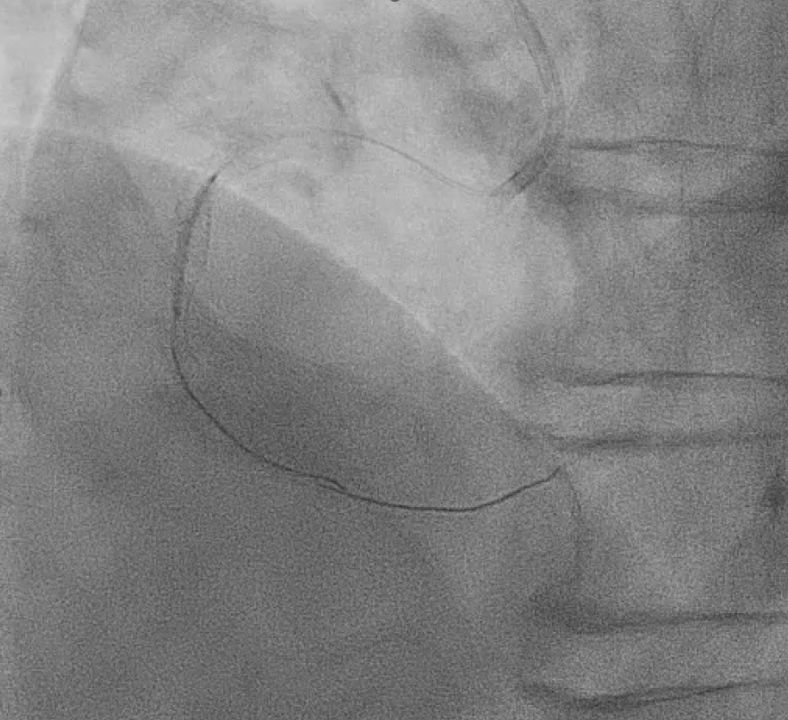

Right distal radial artery was used for access with a 6 Fr JR 3.5 guiding catheter. Anticoagulation was given to keep ACT >250 seconds and dual antiplatelet therapy was continued. A Runthrough wire crossed the diffusely calcified RCA lesion from proximal to distal. Sequential predilation with 2.0–3.0 mm non-compliant balloons was performed to assess vessel compliance.IVUS showed heavy concentric calcification with a minimal lumen area of 3.3 mm©÷. Calcium modification was done using a 4.0 ¡¿ 12 mm intravascular lithotripsy balloon with a total of 70 pulses, achieving good luminal expansion. Two drug-eluting stents were then implanted: 3.5 ¡¿ 50 mm at mid–distal RCA and 4.0 ¡¿ 24 mm at proximal–mid RCA, followed by high-pressure post-dilation up to 20 atm.After optimization, angiography revealed Ellis class II–III perforation at mid RCA. A 7 Fr system with Guideliner support was used for bailout. A 3.5 ¡¿ 19 mm covered stent was deployed to seal the perforation, followed by additional dilation. Because of residual contrast leakage, another 3.5 ¡¿ 16 mm covered stent was placed at proximal RCA, achieving complete sealing.Final IVUS confirmed good stent expansion and apposition. Angiography showed less than 30% residual stenosis with TIMI 3 flow.